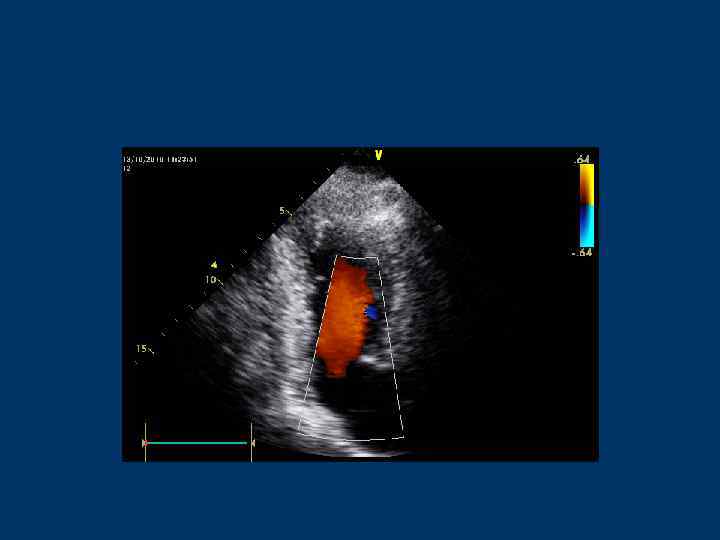

Аортальный клапан и выносящий тракт ЛЖ (LVOT) • Парастернальная позиция по длинной оси ЛЖ • Апикальная 5 -камерная позиция • Апикальная 3 -камерная позиция

Трансаортальный поток

Выносящий тракт ЛЖ (LVOT): Контрольный объем – в выносящем тракте ЛЖ под створками АК Аортальный клапан: Контрольный объем – между створками АК или в аорте не ниже 1 см

Скорость потока через АК - 1, 35 м/с (1, 0 -1, 7) Скорость потока в ВТЛЖ – 0, 9 м/с (0, 7 -1, 1)

Выносящий тракт ЛЖ Скорость потока 0, 8 -1, 2 м/с